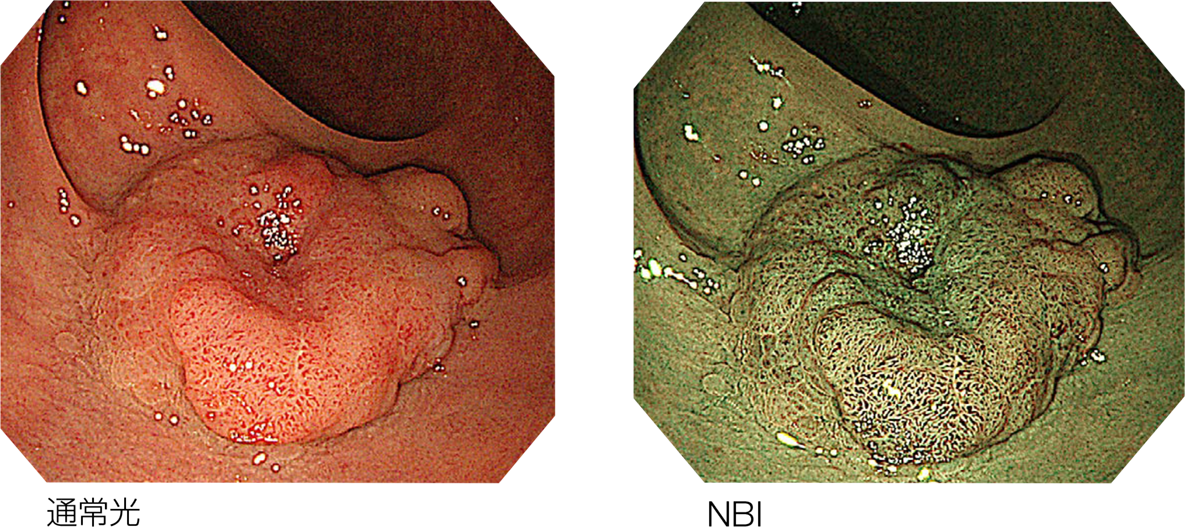

-                高精細なHD画像により快適な処置をサポートハイビジョン対応CCDを搭載し、高精細な画像を提供。処置精度の向上に貢献します。